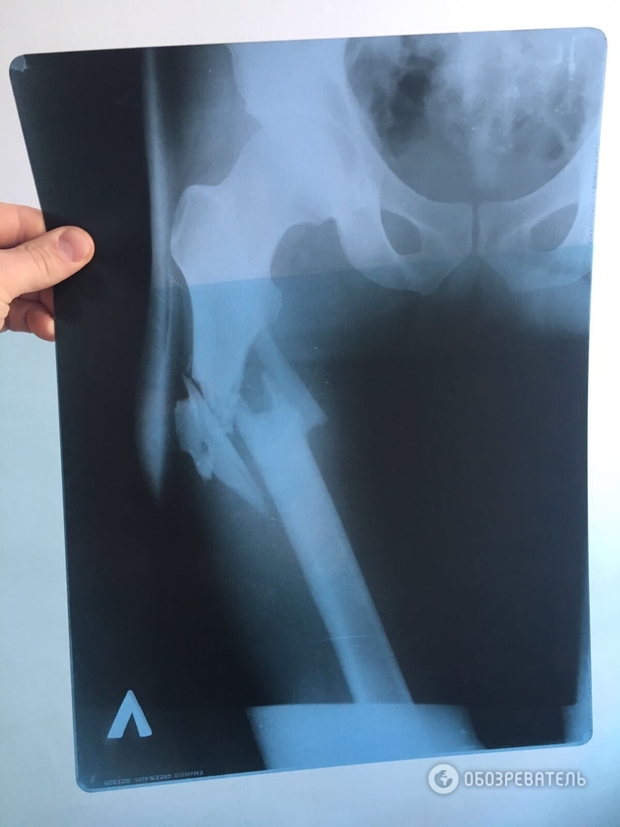

Врач, оперировавший Вячеслава Химикуса, которого ранил из пистолета народный депутат Сергей Пашинский, на допросе подтвердил, что на месте перелома у пострадавшего обломки кости смещены вниз от таза.

Он также подчеркнул, что данный факт подтверждает, что Пашинский выстрелил сверху в ногу Химикусу, а не из положения лежа, как нардеп утверждал ранее.

Напомним, "Обозревателю" удалось заполучить также рентгеновский снимок простреленной ноги Химикуса и заснять пулевые отверстия на его штанах. Учитывая положение входного и выходного отверстий от пули, можно предположить, что пуля "шла" сверху вниз.